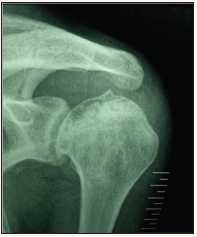

Figure 1: True anterior-posterior (AP) view in case 1: subchondral sclerosis and radiolucent area in humeral head.

Radiographic evaluation: Standard radiological diagnoses include conventional x-ray images. True anterior-posterior (AP) view (Figure 1) showed subchondral sclerosis and a radiolucent area in humeral head. Also, there were some degenerative changes in the articular surface of humeral head. MRI determined the avascular necrosis of humeral head (Figure 2).